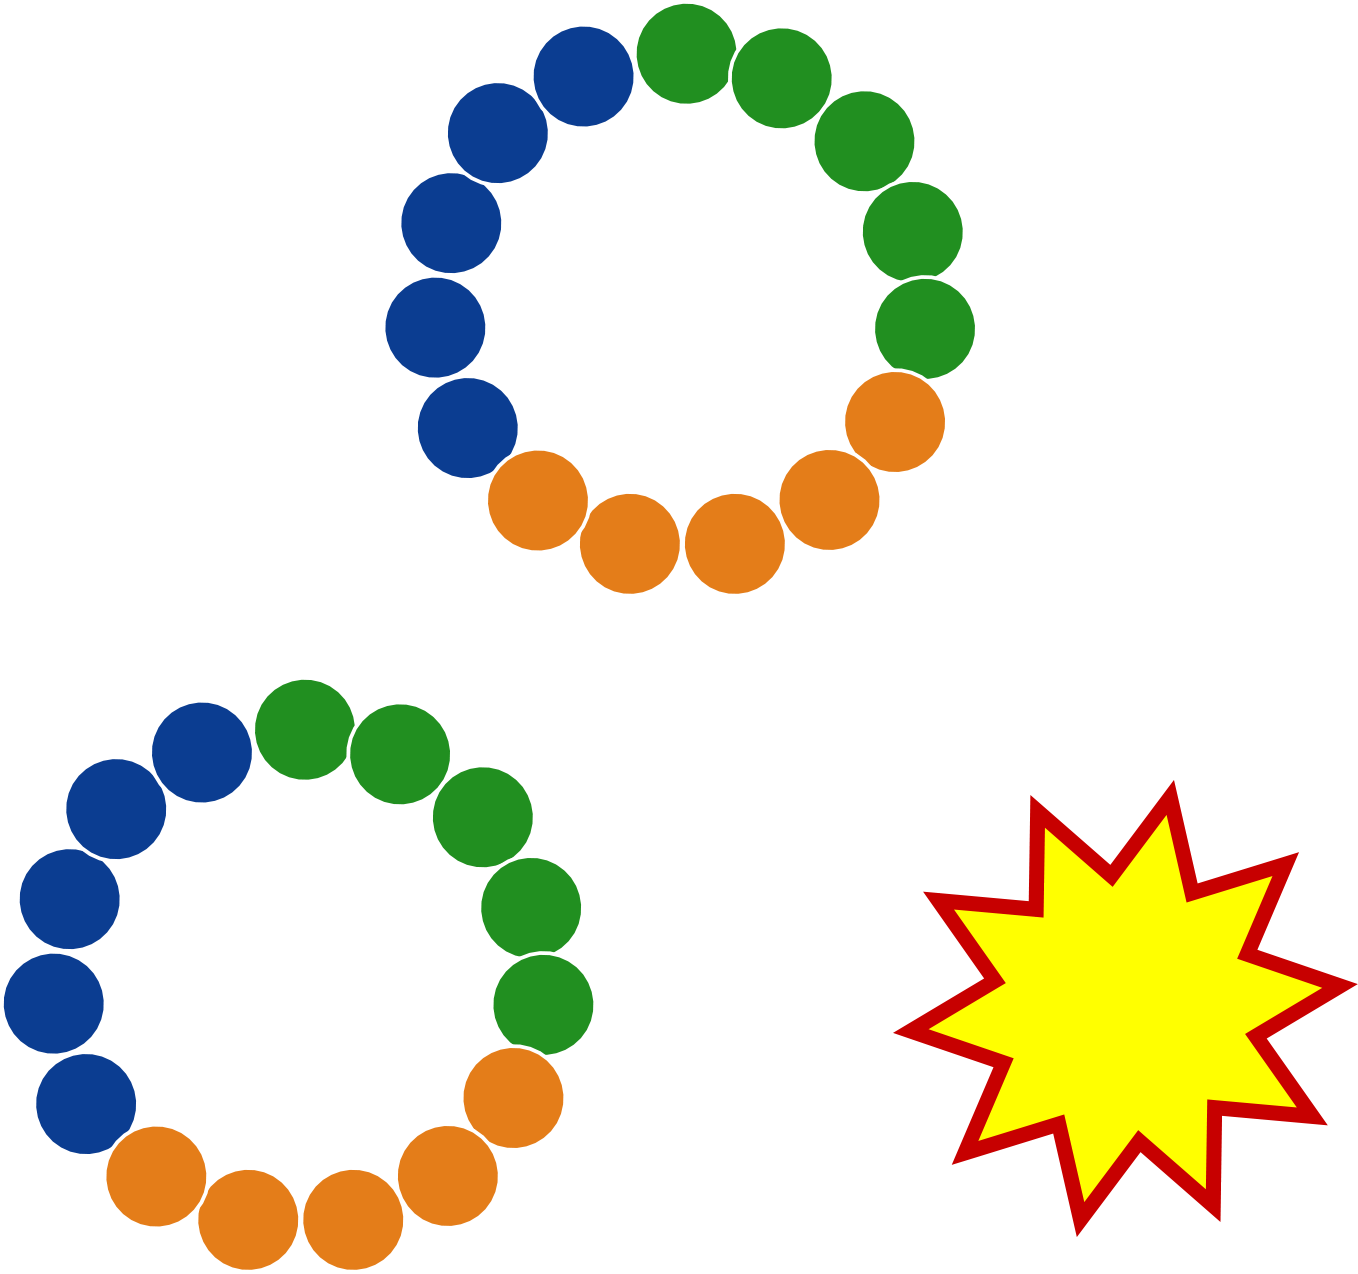

✦ rapid internalization: reduced toxicity by preventing premature release of chemotherapy drug payload

➥ bivalent and/or biparatopic formats deliver payload intracellularly faster than monovalent formats

"Fast In / Fast Out" mechanism

increases tumor uptake and reduces toxicity

Unimpeded renal clearance due to

100% D-amino acids

✦ low renal uptake: after tumor saturation, remaining drug conjugate rapidly cleared through kidneys

➥ 100% D-amino acid peptides are poorly recognized by renal scavenger receptors